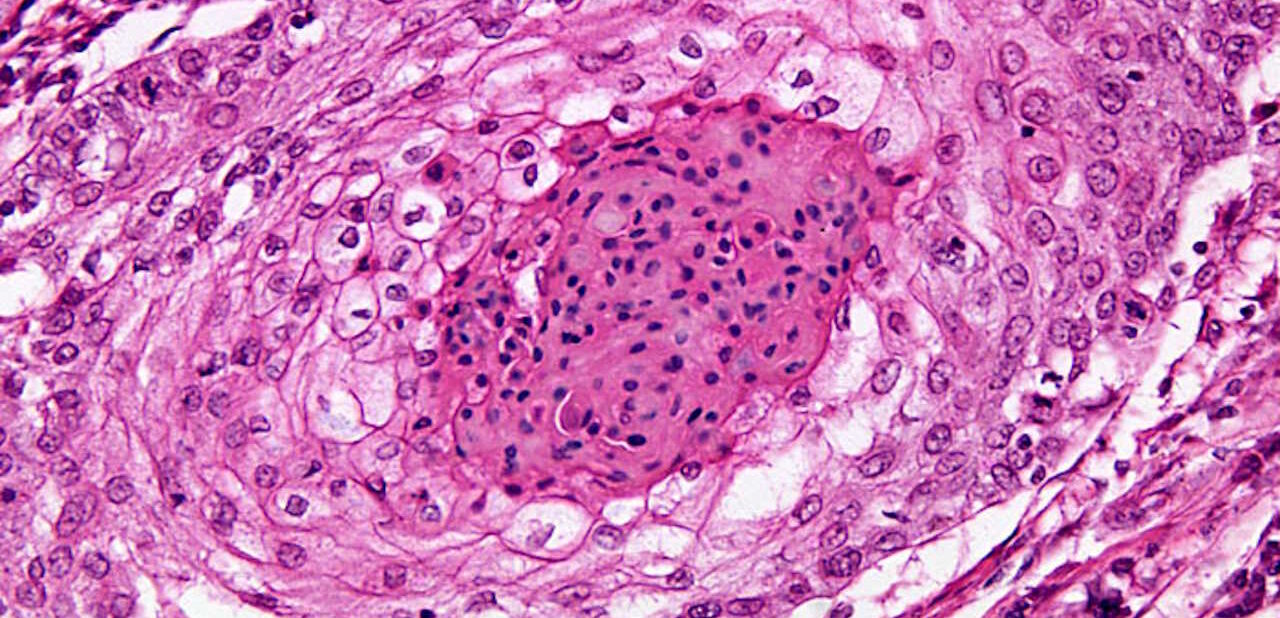

Біофізики вивчили, як ракові клітини здатні проникати в сусідні тканини через надзвичайно вузькі щілини між клітинами. Вони просувають себе вперед і протягують решту клітини за собою. Це стало можливим завдяки дослідженням клітин у гідрогелі з порою, яка іноді була менша за середній розмір клітинного ядра. Результати можуть надати більше інформації про утворення метастазів, коли ракові клітини прослизують між клітинами та волокнами міжклітинної речовини, осідаючи в сусідніх органах. Результати дослідження опубліковані в журналі Science Advances.

Дослідження руху ракових клітин шкіри людини в гідрогелі показало, що клітини перемикаються між двома способами руху — проштовхуванням і протягуванням — завдяки змінам у будові цитоскелета, який підтримує форму клітини і забезпечує її рух. При проходженні через дуже вузькі пори, форма ядра змінюється з витягнутої на стиснуту, і його об’єм може зменшуватися на 11 відсотків.